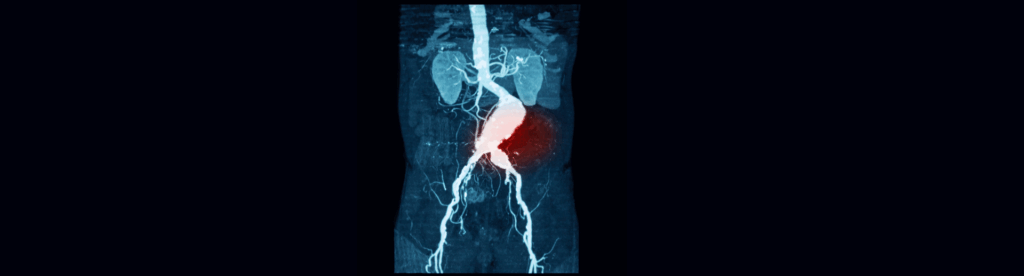

Aνεύρυσμα κοιλιακής αορτής είναι η πάθηση κατά την οποία προκαλείται διάταση του τοιχώματος της κύριας αρτηρίας που διέρχεται από την κοιλιακή χώρα και μεταφέρει το αίμα από την καρδιά σε όλο το σώμα. Πρόκειται για μια σιωπηλή αλλά δυνητικά απειλητική κατάσταση, καθώς η αορτή είναι το μεγαλύτερο αιμοφόρο αγγείο του σώματος και η ρήξη της μπορεί να αποβεί μοιραία. Στις περισσότερες περιπτώσεις, το ανεύρυσμα παραμένει ασυμπτωματικό, με τον εντοπισμό του να γίνεται τυχαία κατά τη διάρκεια απεικονιστικών εξετάσεων. Ωστόσο, όταν μεγαλώσει ή προκαλέσει συμπτώματα, είναι απαραίτητη η χειρουργική παρέμβαση.

Η χειρουργική επέμβαση πραγματοποιείται μέσω μιας τομής στην κοιλιακή χώρα, η οποία επιτρέπει στον χειρουργό να έχει άμεση πρόσβαση στην αορτή. Το ανευρυσματικό τμήμα της αρτηρίας αφαιρείται και αντικαθίσταται με ένα συνθετικό αγγειακό μόσχευμα, το οποίο συρράπτεται στα υγιή άκρα του αγγείου. Η όλη διαδικασία διαρκεί αρκετές ώρες και απαιτεί γενική αναισθησία.